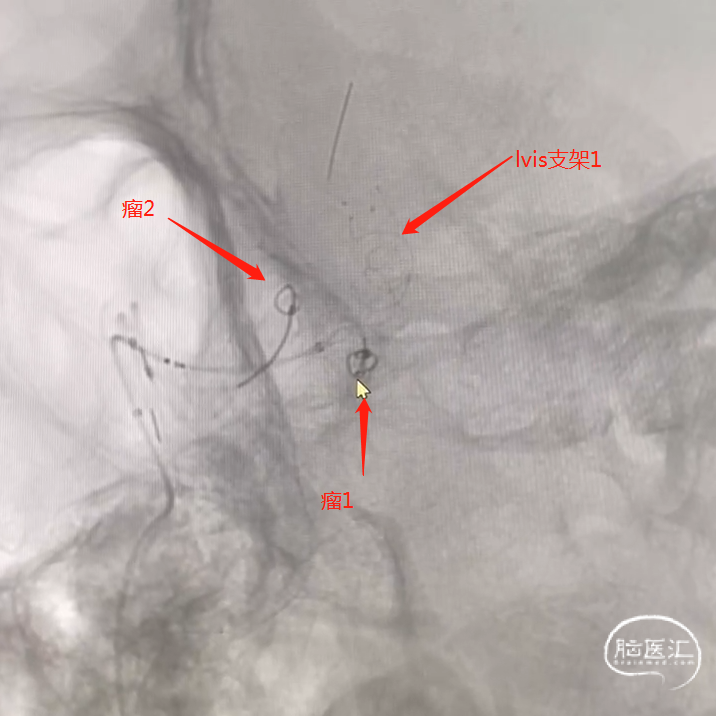

【病例夹】王飞教授:原始三叉动脉瘤栓塞

手术过程